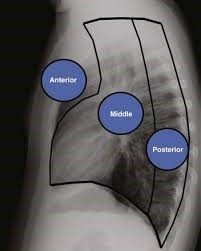

Divararalığının hissələri ilə əlaqədar müxtəlif təsnifatlar var. Ən sadəsinə görə divararaqlığı şərti olaraq 3 hissəyə ayrılır (Şəkil 1,2):

Şəkil 1,2. Divararalığının hissələri

Ön divararalığı

Ön divararalığı döş sümüyünün arxası ilə perikard və böyük damarlar arasında olan sahədir. Burada timus vəzi, daxili döş arteriyaları, limfa düyünləri, kövşək toxuma və piy toxuması yerləşir.

Bu hissədə ən çox rastlanan törəmələr – timoma, limfoma, teratoma və tiroid törəmələridir.

Orta divararalığı

Orta divararalığı perikard ilə döş fəqərələrinin ön səthi arasındakı sahəyə deyilir. Burada ürək və perikard, böyük damarlar, traxeya və bronxlar, qida borusu, diafraqmal sinirlər, limfa düyünləri və kövşək toxuma yerləşir.

Bu hissədə ən çox rast gəlinən törəmələr limfatik törəmələrdir (sarkoidoz, limfoma, metastatik).

Arxa divararalığı

Arxa divararalığı döş fəqərə cisimləri ilə qabırğalar arasındakı sahəni əhatə edir (fəqərə-qabırğa şırımı). Burada qabırğaarası sinir və damarların proksimalı, simpatik qanqlionlar və kələf, limfatik axacaq, limfatik düyünlər və kövşək toxuma yerləşir.

Bu hissədə ən çox rast gəlinən törəmələr neyrogen törəmələrdir.